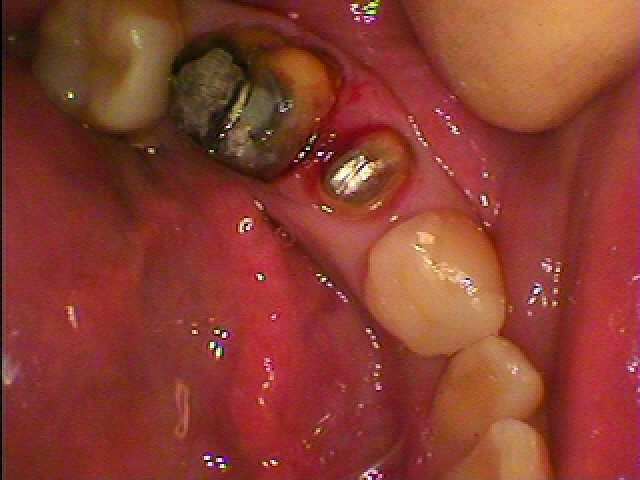

被せを外していきます

中はひどく痛んでる歯もあります

虫歯で真っ黒になっています

手前の歯も虫歯があり治療していきます